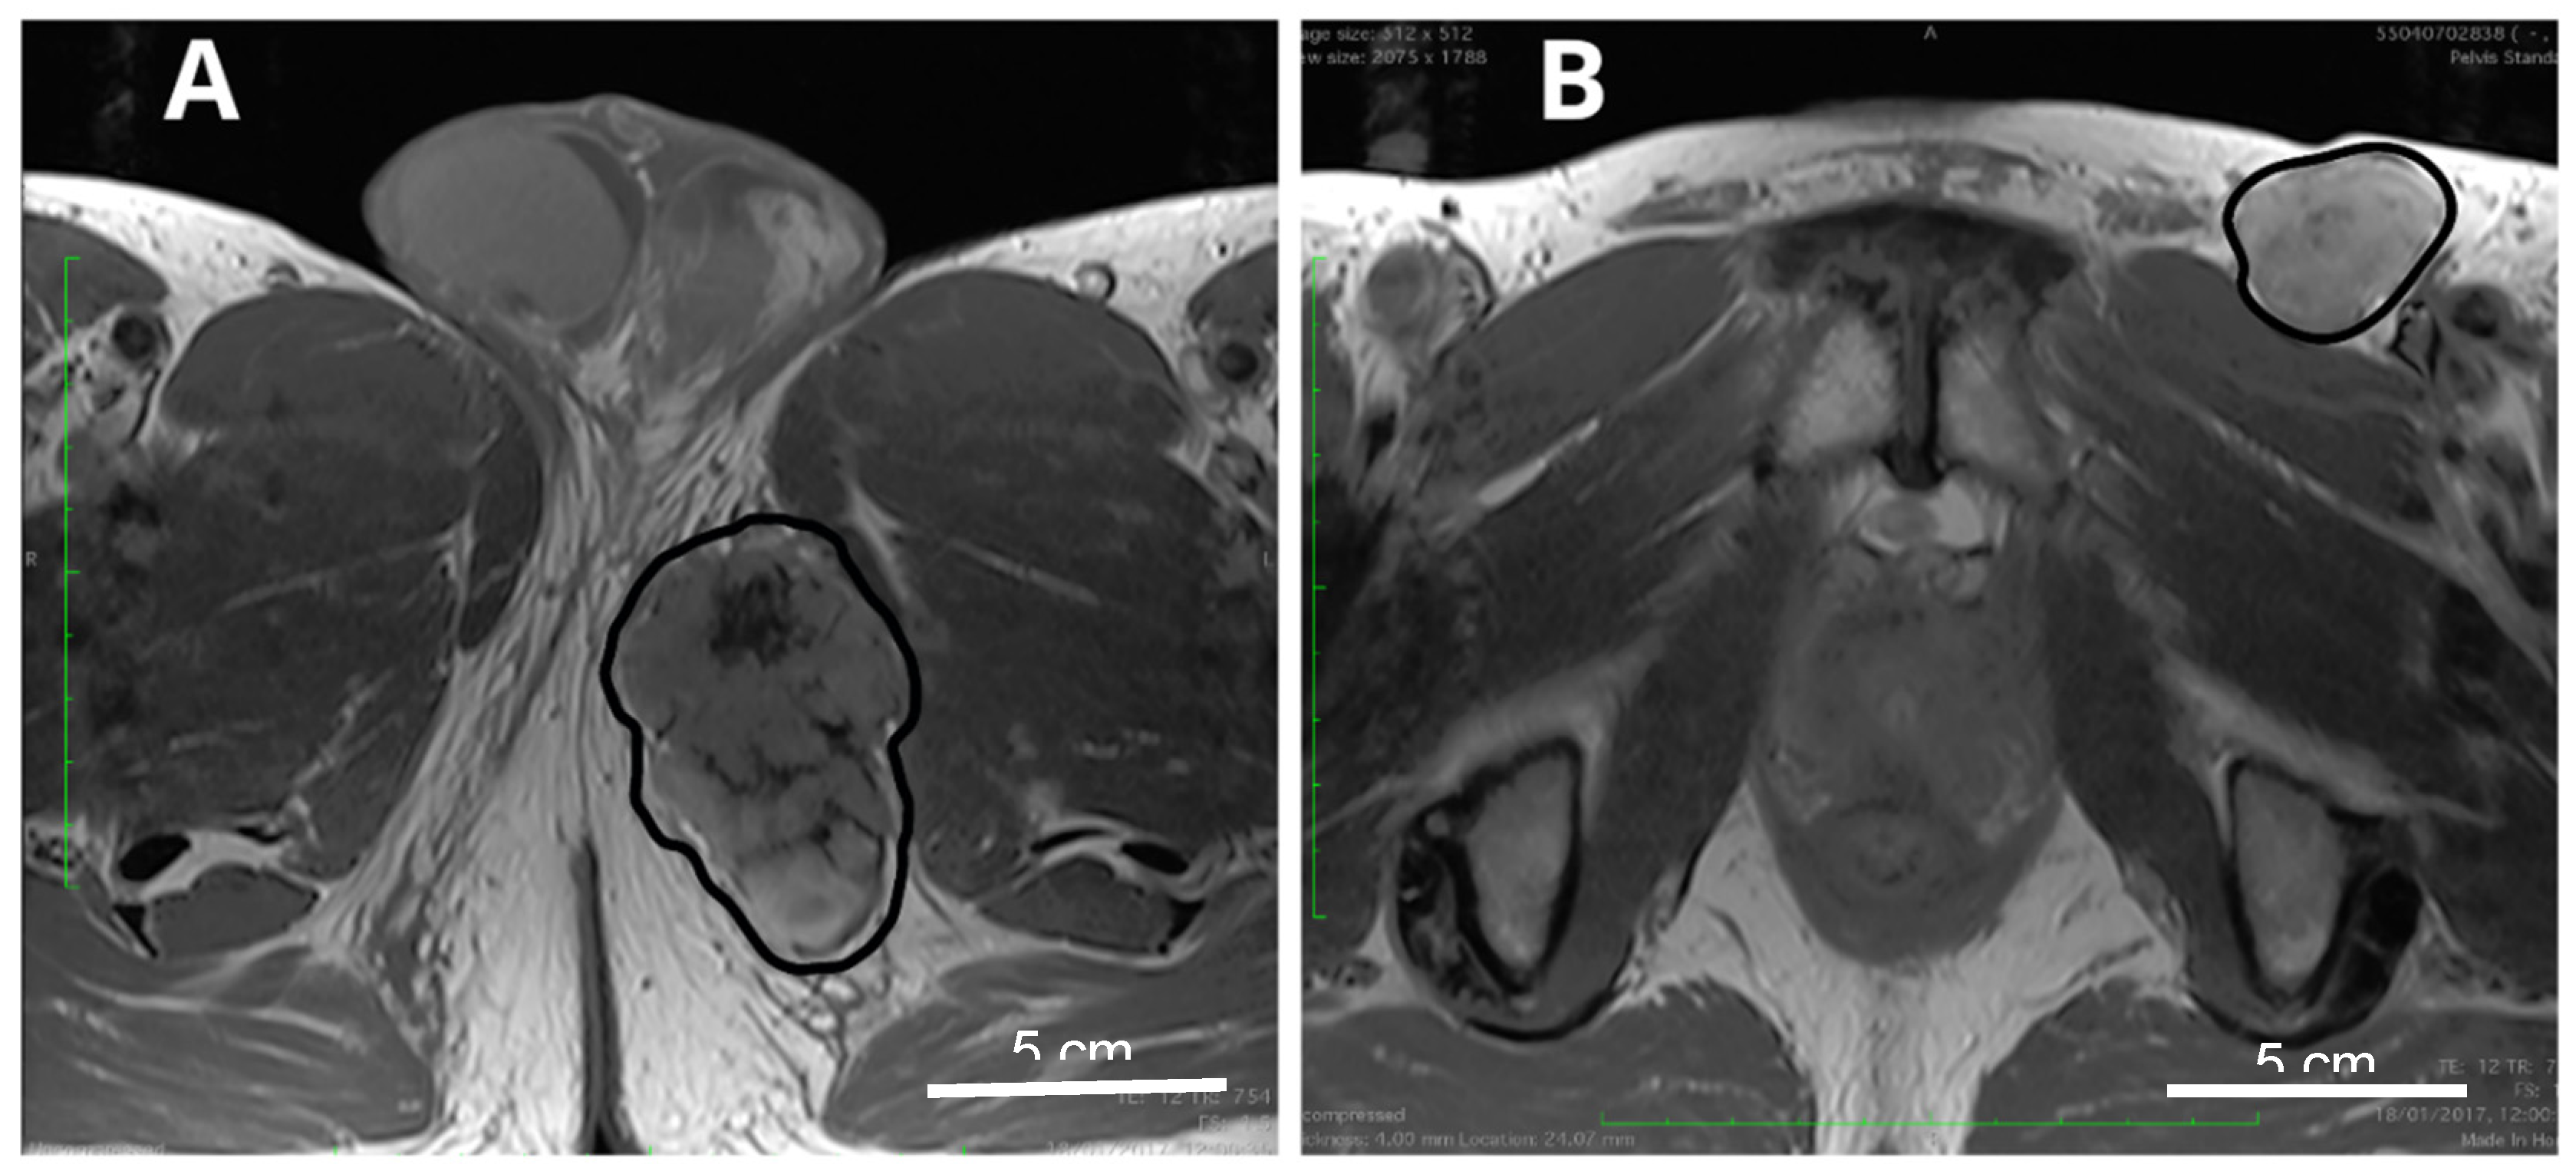

5.1. Radiotherapy of the Primary Tumor

5.2. Radiotherapy of Recurrent Disease